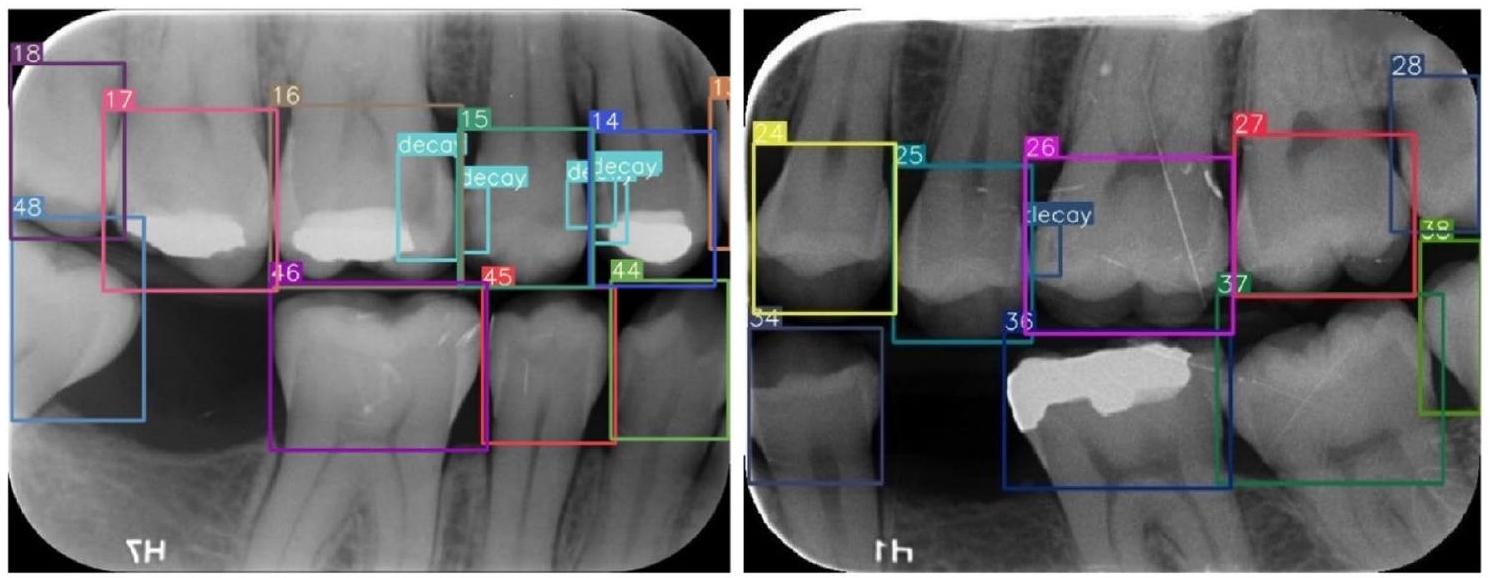

Image evaluation and data labeling

to Federation Dentaire International (FDI) tooth notation system (16-17-18-26-27-28-36-37-38-46-47-48 (molars), 14-15-24-25-34-35-44-45 (premolars) and 13-23-33-43 (canines)). Also, caries lesions labeled as decay in digital bitewing images. While in the data labeling procedure,

annotators reviewed the bitewing images at the same time and as a result of the agreement, labeling was processed (Fig. 3).